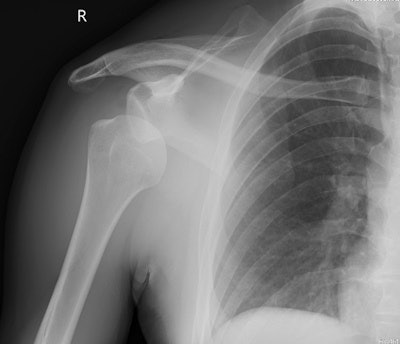

Hamstring strains and injuries are common in fast bowlers. Injuries of the hands/fingers such as avulsion fractures and dislocations are usually a result from a player catching the ball and are common. Rotator cuff injuries are often seen in fast bowlers and fielders, with labrum injuries commonly seen in fielders.